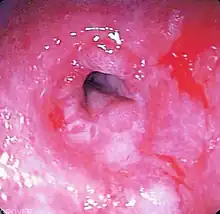

La fibroscopie

L'endoscopie digestive haute ne pose pas le diagnostic de reflux mais permet de déterminer l'existence ou non d'une lésion œsophagienne secondaire à celui-ci, tels qu'une œsophagite ou une sténose (rétrécissement) par exemple. Cet examen peut être totalement normal, même en cas de reflux avéré.

La fibroscopie permet de classer la maladie suivant la classification de Los Angeles[47].

- Grade 0 : anamnèse typique de reflux sans lésions muqueuses détectables à l’endoscopie.

- Grade A : une ou plusieurs lésions muqueuses, inférieures ou égales à 5 mm

- Grade B : au moins une lésion muqueuse de plus de 5 mm mais sans aucune confluence entre les sommets des 2 plis.

- Grade C : au moins une érosion continue entre les sommets de 2 plis ou plus, mais non circonférentielle.

- Grade D : lésion muqueuse circonférentielle.